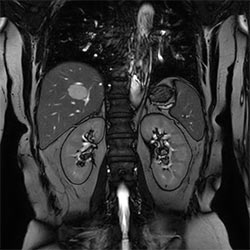

In a society where reimbursements are declining and chronic conditions lead to increased MR procedures and longer waiting times, there is ever increasing pressure on the radiology department. Today, further attempts to accelerate, compromise image quality or are limited to a narrow range of scans. Therefore, to meet the increased demand for productivity, a technology break-through in acceleration is still required. Leveraging our long standing leadership position in speed (i.e. SENSE), Philips brings compressed SENSE, a breakthrough in productivity.

Compressed SENSE increases the examination efficiency thanks to a shorter scan time with no change in image quality”

Sachi Fukushima, RT, Kurashiki Central Hospital, Japan

Learn more about the main principles of Compressed SENSE and how it introduces a paradigm shift in productivity, how Compressed SENSE was designed around image quality, and how it advances productivity for clinical MR imaging.